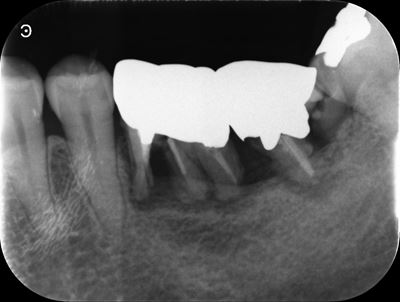

左下6番X線画像

移植歯レプリカの試適(移植床の適合確認):症例1-2